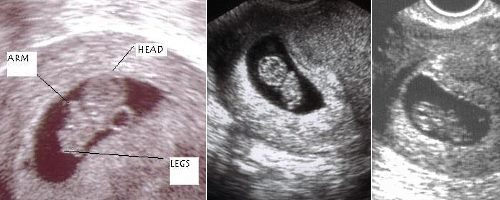

Развитие эмбриона на 8 неделе беременности